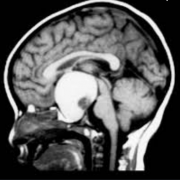

INC旗下国际神经外科顾问团(WANG)专家成员James T. Rutka教授在论文中表示:了解鞍区和鞍上区解剖是选择颅咽管瘤较好手术入路的关键...

颅内颈动脉位于视神经的外侧。颈动脉常突出于蝶窦外侧壁,视神经管突出于蝶窦上外侧,三叉神经二分支突出于蝶窦下外侧。视神经、动眼神经、颈动脉...

儿童颅咽管瘤是一种少见的、鞍区或鞍旁区胚胎性畸形的低级别组织学恶性肿瘤。由于颅咽管瘤与视交叉、脑垂体和下丘脑在解剖学上的邻近关系,其不良...

儿童期颅咽管瘤 是少见的,蝶鞍或鞍旁区域的胚胎发生畸形,伴有低度组织学恶性肿瘤。颅咽管瘤由于接近视交叉,脑垂体,经常影响儿童的生活质量(...